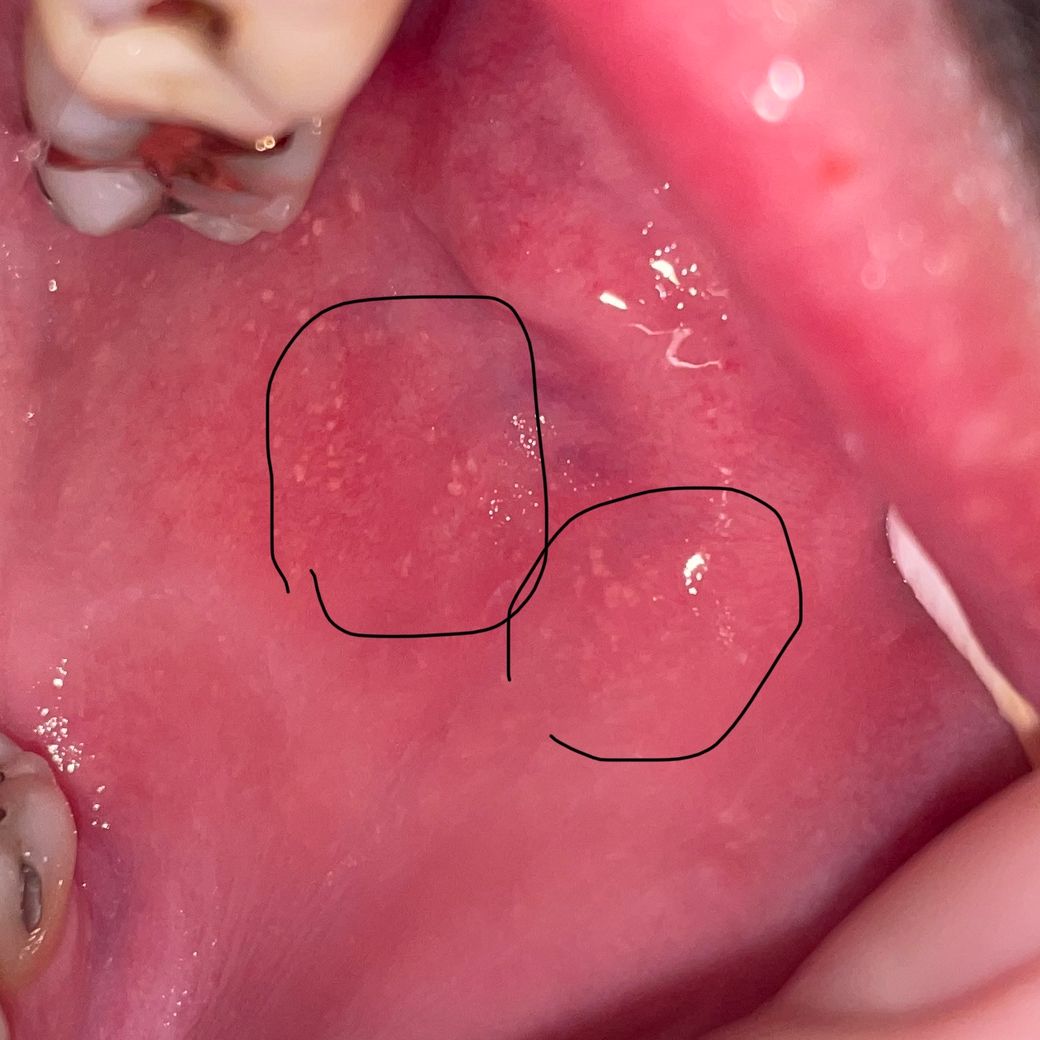

볼 점막에 하얀 돌기들 악성병소 인가요?

통증도 가끔씩 따끔거리는데 시간이 지나면 없어지는건지 악성병소 구강암 같은 위험한 것인지 궁금합니다 인터넷에 찾아보니 포다이스과립일 수도 있다는데 따끔고리는 통증이 있어서 심각한건가요?

포다이스 과립의 가능성이 높겠습니다

악성 가능성은 육안으로는 높지 않으나

확진여부는 조직검사를 해봐야 알 수 있습니다